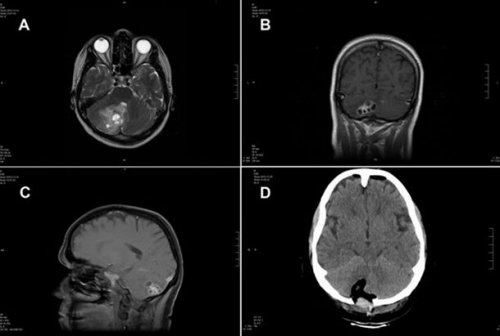

15. Солитер в мозге

Розмари Альварес (Rosemary Alvarez) полагала, что у нее опухоль мозга. Когда врачи отправились на операцию, вместо этого они обнаружили солитера, прикрепленного к стволу головного мозга. Они смогли убрать его, и женщина полностью выздоровела. Видимо, червь попал в организм после употребления пищи, загрязненной человеческими фекалиями.